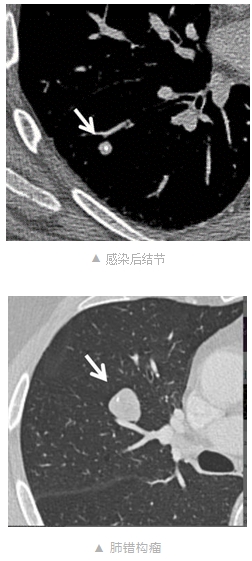

2.超过95%以上的肺结节是良性的,是偶然发现的肺结节,绝大部分就是良性的结节,不需要手术干预。比如我在这里附上的图1和图2,这两类结节就是典型的良性结节,一个是感染后的结节,一个是错构瘤,就是典型的良性结节,不需要随访复查。